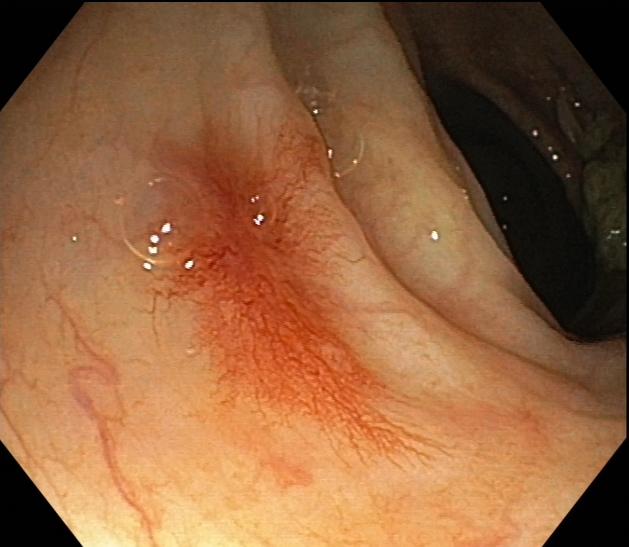

●肠镜检查示:慢性乙状结肠;直肠黏膜炎;结肠蜘蛛痣;外痔。

肠镜显像3

2.皮肤粘膜未见肝掌、蜘蛛痣,结肠镜检可见蜘蛛痣。

●此患者皮肤黏膜未见蜘蛛痣可能与治疗后肝功能好转有关;肠道蜘蛛痣与门脉高压性胃肠血管病有关,最主要的病理基础和形成条件是门脉高压,临床上遇到门脉高压患者内镜下出现此类胃肠道表现:血管病变,非炎性病变或炎症轻微,可考虑本病。主要的治疗方法:口服药物:β受体阻滞剂、生长抑素及其类似物降低门脉压力、TIPS分流或断流术、外科门脉减压术有一定的疗效。

肠道蜘蛛痣多见于门脉高压性肠病患者中,直肠、肛管静脉曲张,门脉高压性直肠静脉曲张往往引起下消化道出血;内镜下见多发性樱桃红病变,血管呈蜘蛛样血管扩张以及退行性改变;蜘蛛痣与肝肺综合征、酒精性肝病、肝炎肝硬化、门脉高压性胃肠病、食管胃静脉曲张破裂出血等都有相关性,我院曾收治过因肠道血管病变导致消化道出血的患者,所以临床上仍应高度警惕此类并发症,出现肠道蜘蛛痣时应根据病史、生化检查、影像、内镜等检查综合分析评估,动态观察,谨防出血。